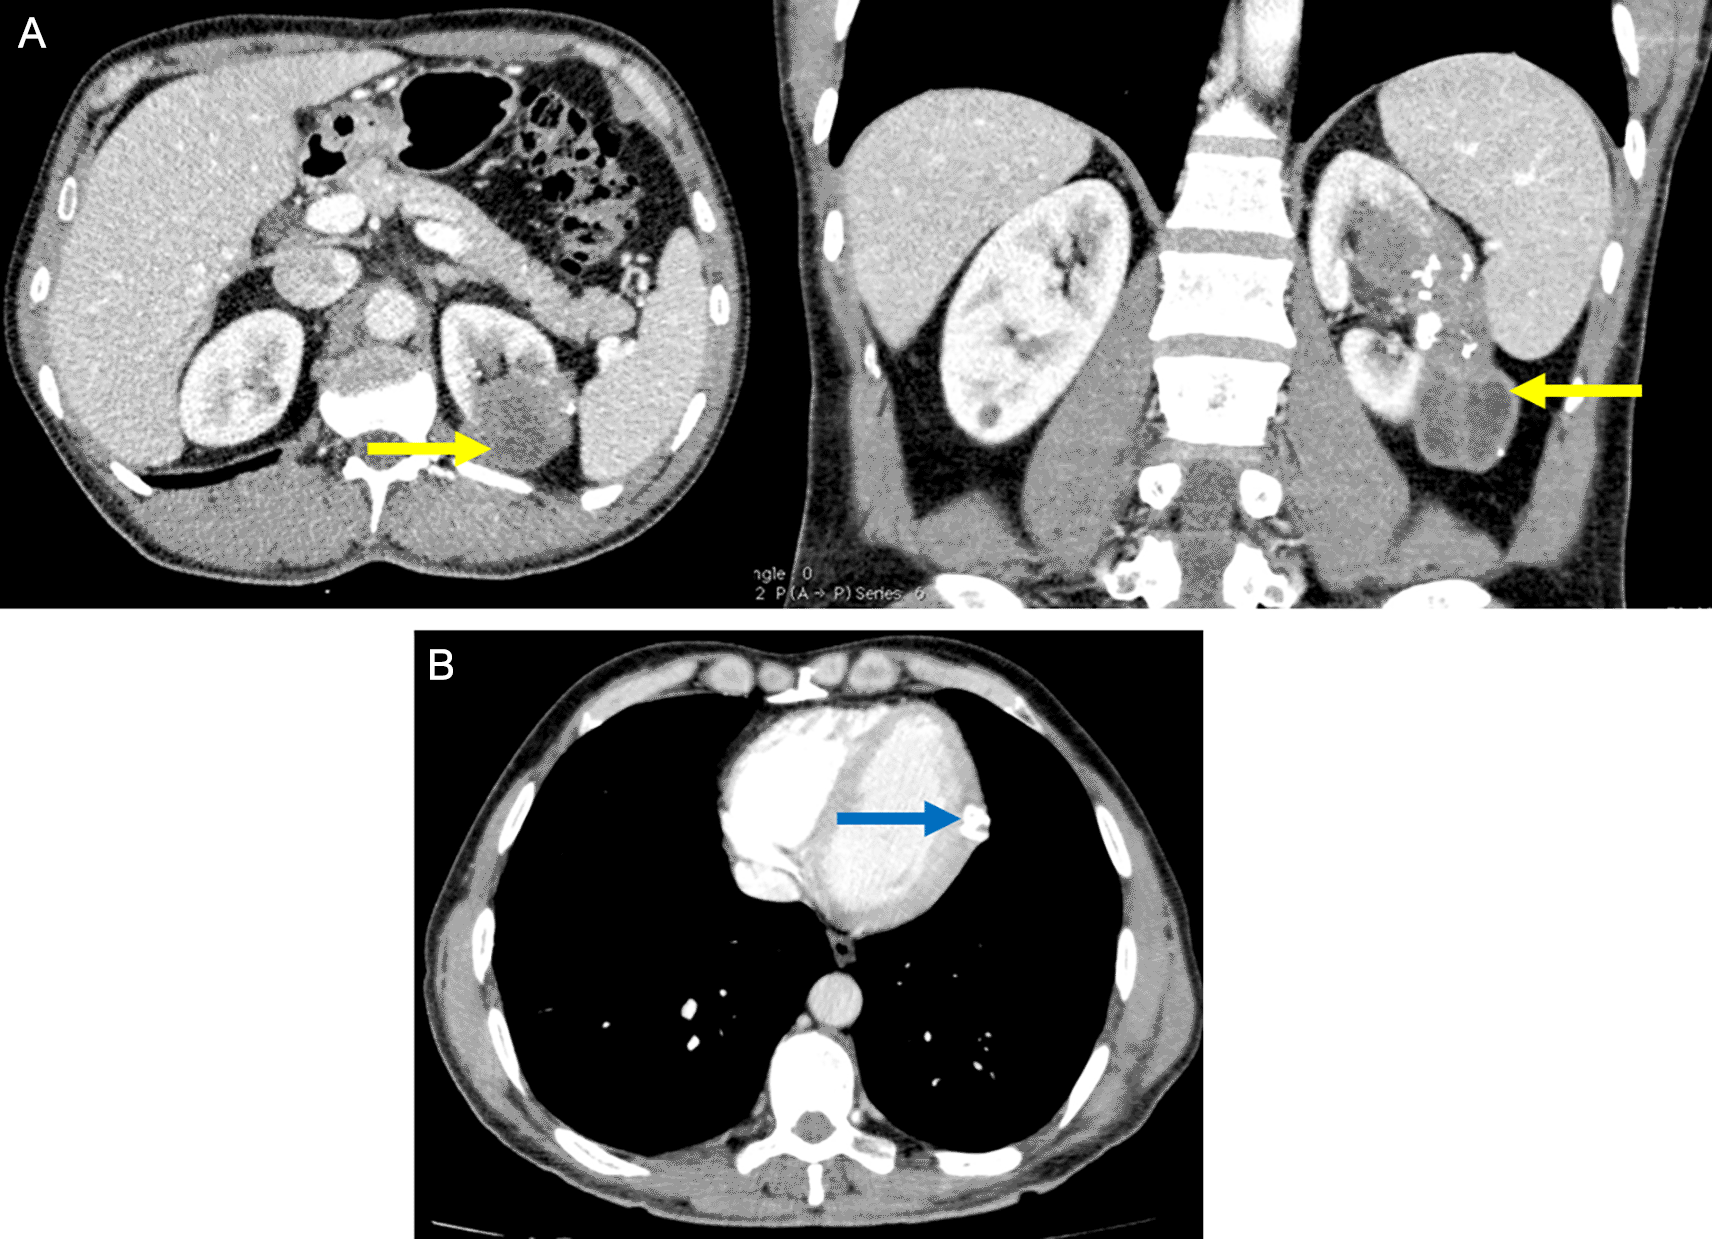

The patient was followed up in the abdominal surgery department for a multiple organ hydatidosis that included 13 hydatid cysts: the lungs, the liver (Figure 1), the left heart ventricle, the left kidney (Figure 2), the abdomen cavity, muscles (psoas, adductors), and subcutaneous gluteal area. The majority of these cysts was already treated surgically and some are still pending to be removed (Table 1). The patient has received oral Albendazole 400 mg twice-daily for 2 years.

Heart involvement is uncommon and accounts for less than 0.5% of the cases, it is usually part of a disseminated infection.2 This localization is potentially fatal without surgical treatment but fortunately with the improvement of surgical techniques, its morbidity has declined drastically. Our patient underwent open heart surgery to remove a left ventricular wall cyst without local recurrence and a post-surgical echocardiography without abnormalities.

The invasion of the myocardium usually occurs hematogeniously through the coronary arteries and since the majority of the population have a left dominant circulation, the left ventricle is the most commonly involved part of the heart (60%),3 other explanation is the dissemination from the lungs either following a pulmonary vein rupture and migration of the cysts4 or by a direct contact with hydatid cysts originating from the lung.5

Renal involvement is also rare (2–3%) and it is usually associated to a disseminated disease, they are most commonly asymptomatic, like the case of our patient. The diagnosis was made by an abdominal CT which has a sensitivity of 98% to diagnose hydatid disease.6